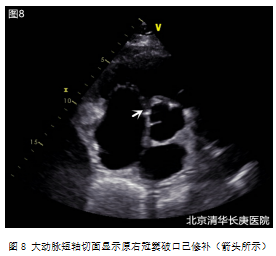

e.术后处理:返回CCU继续监护治疗,待神志、呼吸及循环系统稳定后撤离人工呼吸机(呼吸机辅助时间6小时),预防性静脉滴注抗生素3天,复查血象、胸片及超声心动图(图8),超声心动图重点观察主动脉窦形态、分流是否消失及各瓣膜功能等;